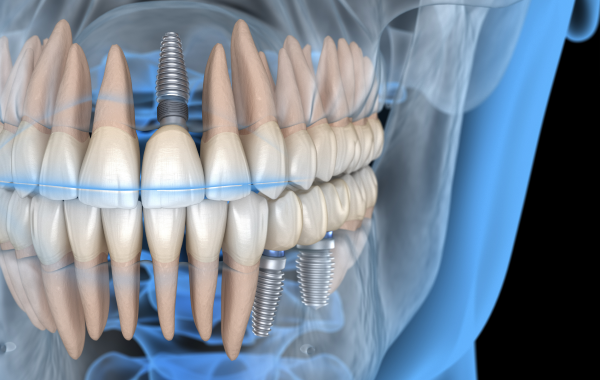

Un implant dentaire est une racine artificielle, le plus souvent en titane. Il est placé dans l’os de la mâchoire pour remplacer la racine d’une dent absente. L’implant permet ensuite de fixer une couronne, un bridge ou une prothèse. Il contribue à retrouver une mastication efficace et un rendu esthétique naturel.

L’implant est inséré dans l’os de la mâchoire lors d’un acte chirurgical maîtrisé. Cette intervention est généralement bien tolérée et réalisée dans des conditions de confort adaptées.

Après la pose, une période de cicatrisation est nécessaire afin de permettre à l’implant de s’intégrer solidement à l’os. Cette étape est essentielle pour assurer la stabilité à long terme du traitement.

Une fois l’implant parfaitement intégré, une couronne dentaire est fixée dessus. Elle est conçue pour s’harmoniser naturellement avec les dents existantes, tant sur le plan esthétique que fonctionnel.